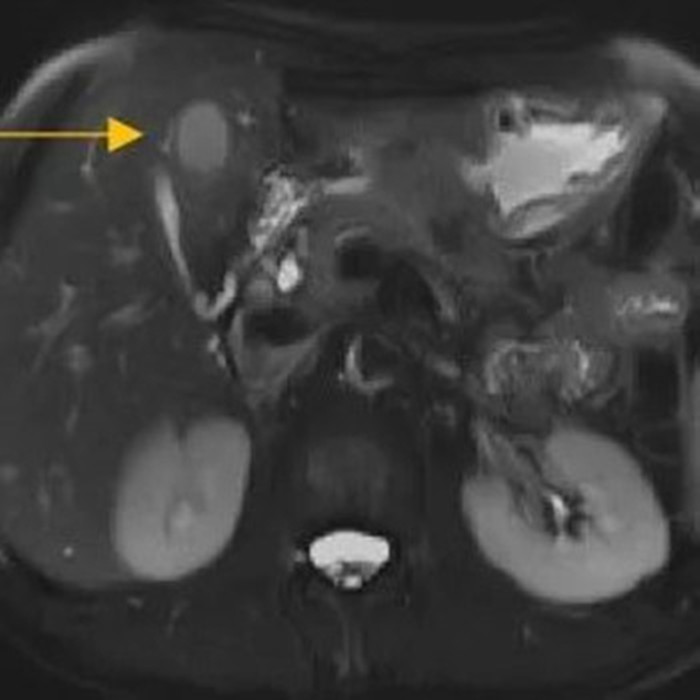

住院后經(jīng)胸腹部CT檢查,提示周先生胃部巨大腫塊穿破胃腔,可能累及到結腸,同時合并有胃旁淋巴結轉移、肝臟的轉移??吹竭@個檢查報告后,周先生和他的愛人一下子就泣不成聲了。

治療前肝臟的轉移灶

經(jīng)過6個周期,前后4個月的治療,周先生再次復查CT,提示胃部腫瘤,轉移的胃旁淋巴結、肝臟腫瘤都有明顯縮小,營養(yǎng)狀況良好,能正常進食,體重增加了6斤,精神狀態(tài)比原先好了很多。